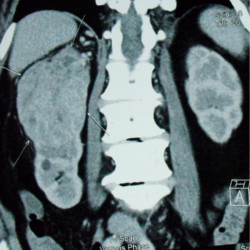

Small Kidney Tumour

If the tumour is small or if it is present in solitary kidney, local resection of tumour with surrounding tissue is done and is called partial nephrectomy.